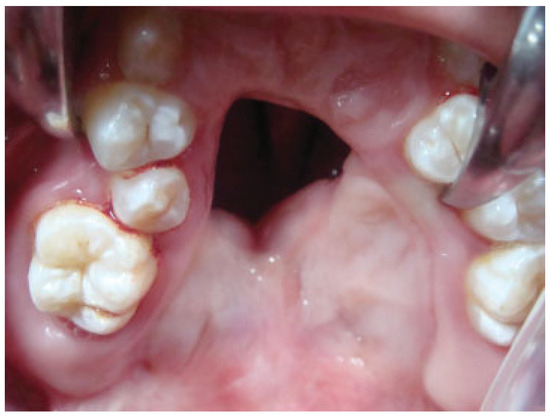

Palatal fistula is a difficult complication after cleft palate repair. The repair of a palatal fistula can be challenging, particularly in wide and recurrent fistulas (Figure 1). Large defects after cleft palate repair produce various symptoms, including regurgitation of fluid into the nasal cavity, hearing loss, and velopharyngeal insufficiency. In these cases, the palatal tissue around the fistula can be quite scarred and in short supply. A variety of reconstructive options are commonly employed, using local flaps of muscle and mucosa or tongue tissue or using distant flaps [1,2,3]. The combination of buccal mucosal flaps and buccinator muscle as an axial myomucosal flap based on the facial artery has been described by Pribaz et al. [2].

Figure 1. Severe palatal fistula after primary palatoplasty in a 7-year-old patient.

Case 11

An 8-year-old boy with a history of bilateral cleft lip and palate presented with an anterior fistula measuring 33 × 19 mm after palatal surgery (Figure 9). The fistula was closed with a left anteriorly based NAMMC flap (Figure 10).